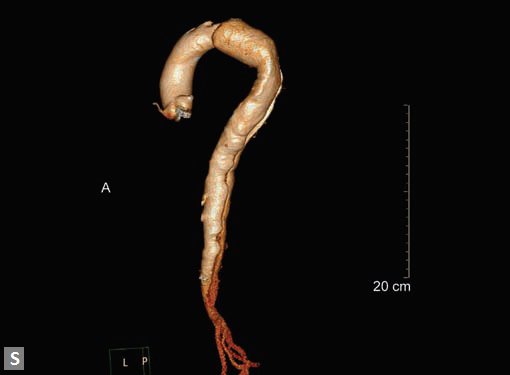

Any part of aorta can get affected by aneurysms. Focal

dilations can be saccular or fusiform. Atherosclerosis is

the most common cause. Tubercular and other infective

aneurysms, traumatic ones are also uncommonly seen. Size

of the aneurysm, proximity to origin of main vessels, relation

with branching and bifurcation, presence of mural thrombus

are the critical information sought on CT.

Contained leak, rupture are the feared complications.

Aortoenteric fistula is a rare but potentially catastrophic

complication. Aneurysmal dilation is common in ascending

aorta (Figs 19W to Y).

CT is also useful in surveillance of diagnosed aneurysms.

Figs 19A to Y (A to C) Scannogram (A), plain (B) and contrast study (C) show partial anomalous pulmonary venous connection; (D to F) Heterotaxy; (G) Aortic occlusion; (H and I) Aortic stents; (J) Aortic dissection with ‘Benz’ sign due to second dissection within the true lumen; (K, L and M) Aortic dissection with thrombus in pseudolumen following catheter angiogram; (N) Aortic dissection involving common carotid arteries and subclavian artery; (O, P, Q and R) Aortic dissection with right renal artery arising from true lumen and left renal artery from false lumen; (S, T, U and V) Stanford B dissection with extension Y to iliac vessels; (W to Y) Aneurysmal dilation of ascending aorta